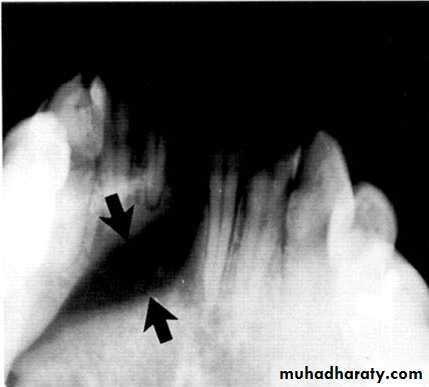

Central giant cell granuloma*A relatively uncommon, non- neoplastic mass in the jaws (intraosseous) producing an expansile radiolucent soap bubble appearance.

*Age; <20 years. Female > Male.

*Teeth are vital, with some root resorption & migration of teeth.

Multilocular appearance, expansion (arrowed) and considerable displacement of the adjacent teeth.

Buccal and lingual expansion (arrowed) and the undulating cortical border.